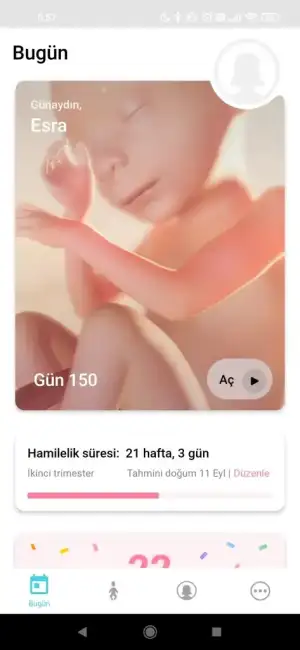

hoca diyo ki pipisi her yerden çıkıyor asgahaha , 21+3 üz bugün 442 gr çıktı , vee tam 150. gün geride kaldı 5.ayı bitirdik gerisi artık sağlıkla kucağımıza almaya ve büyütmeye inşallah